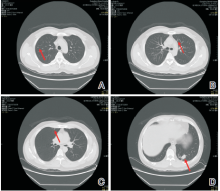

谢松喜:经科内讨论, 决定采用经皮肺穿刺活检+系统化疗+肺部手术+鼻咽部放疗的治疗方案。2013-08-01行经皮肺穿刺活检病理结果为肺浸润性腺癌。科室讨论此患者的诊断考虑为:鼻咽非角化型未分化癌伴双肺转移(cT3N1M1, Ⅳ C期), 左肺腺癌(cT1bN0M0, Ⅰ A期)。2013-08-16行第1周期TPF方案化疗(考虑本化疗方案同时对鼻咽癌及肺癌有效), 第2周期化疗后于2013-09-24复查胸部CT提示:与治疗前对比, 原发灶缩小, 转移灶减少、缩小(见图3)。治疗有效。予以继续完成共4周期TPF方案化疗。化疗结束后于2013-11-08行全胸腔镜下肺叶切除术+肺门纵隔淋巴结清扫术, 术后病理:(左下肺)肺浸润性腺癌, Ⅱ 级, 淋巴结可见癌转移(共1/9, 其中“ 段LN” 1/1)。术后恢复良好, 于2013-12-13开始行鼻咽+颈部调强放疗, 剂量66 Gy/30 F, 2014-01-23结束全程放疗。放疗后定期复查鼻咽MRI提示鼻咽肿瘤消失(见图4)。2014-07-08复查胸部CT示:左肺上叶前段结节较前增大, 考虑恶性可能性大。右肺两个小结节, 变化不大(见图5)。 此时, 我们需要明确:(1)诊断是否要改变?肺部小结节是良性或恶性?是肺多原发癌或鼻咽癌或肺癌转移?(2)左上肺新发增大的肺部结节如何处理?

图5 随访胸部CT新发病灶